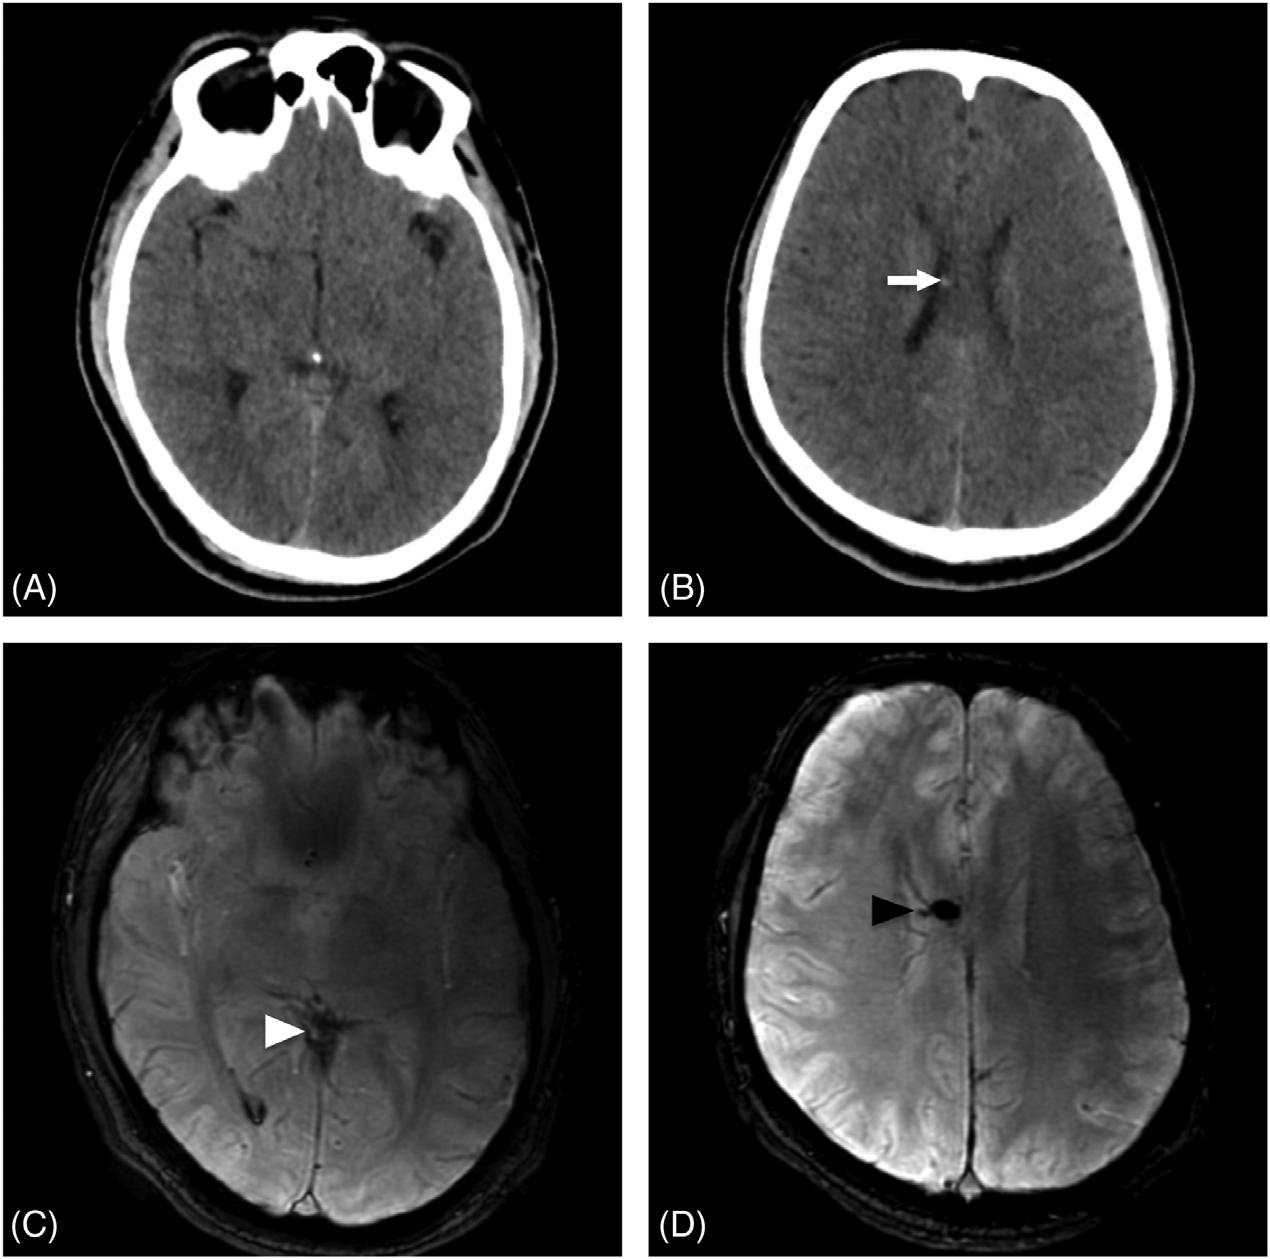

ThepatientunderwentanemergentCTofthehead (Image3)duetothechangeinmentalstatus.Theradiology impressionoftheCTrevealed “extensivevenousgas,which

Computedtomographyofthebrainofa77-year-oldman afterarapidchangeinmentalstatusshowingextensivevenous gas(whitearrows)intherightparieto-occipitalregion.

mayindicategasemboluswithpossibleevolvinginfarctionin therightparietalregion.Nohemorrhageorshift.Further evaluationwithmagneticresonanceimaging[MRI]maybe useful.Largegoiter.” Immediatelytheteamassessedthe patient’scentralvenouscatheterandfoundanuncappedline. Aftertheairwaswithdrawnfromtheline,thelinewas capped.Thepatientwastransferredtotheintensivecareunit atourhospitalforfurthermanagementandahyperbaric medicineconsultation.Heunderwentahyperbaricoxygen therapytreatmentwithresolutionofthegasontherepeatCT head.Afollow-upMRIrevealedmultifocalinfarctsin multiplevascularterritories.